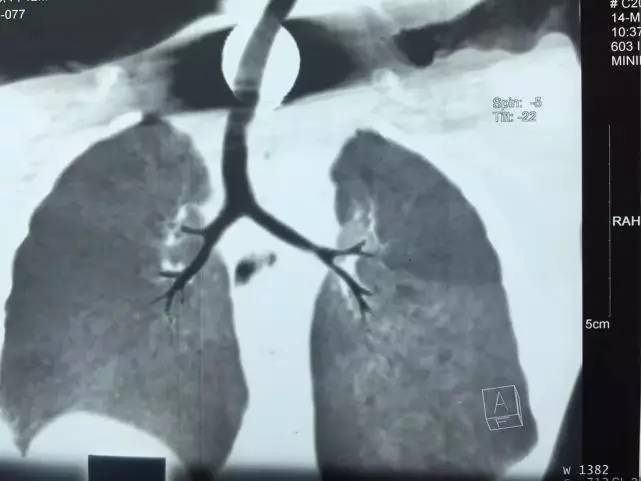

从2016年12月到2017年3月,家人带着他反复在长沙和汨罗的多家县、乡级医疗机构就诊、治疗,直到2017年3月9日,在汨罗市的医院照片怀疑食道有异物,建议转往长沙。于是家人带着彬彬来到湖南省人民医院耳鼻喉头颈外科肖旭平教授处就诊,于3月16日住进耳鼻喉头颈外科一病室。

次日,肖旭平教授带领医务人员为彬彬在全麻下施行急诊食道镜异物取出术,仅花了不到两分钟便顺利取出一枚五毛钱的硬币。由于在孩子体内呆的时间太长,硬币已经发黑,几乎看不出本来面目。